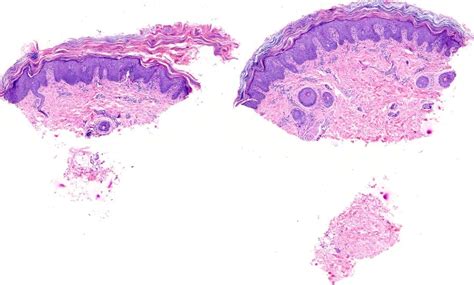

Dermatopathology Society of India: Image of the Month

dermpathindia.org